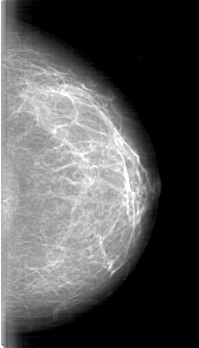

D_4071_1.RIGHT_CC

RIGHT_CC LINES 4906 PIXELS_PER_LINE 2791 BITS_PER_PIXEL 12 RESOLUTION 43.5 OVERLAY